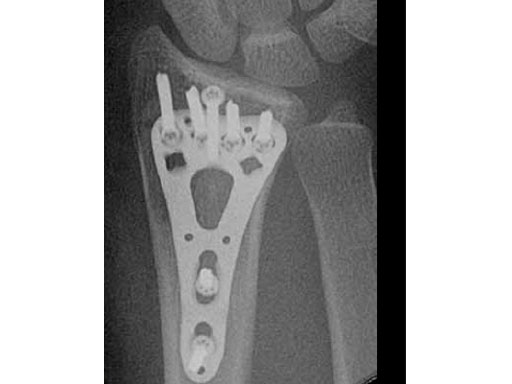

Fig 3ac Postoperative x-rays showing comparison of plate alternatives.

a Four-hole small.

c Five-hole.